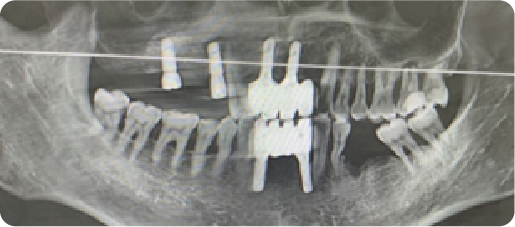

Half Arch Dental Implant Case

BEFORE

VS

AFTER

Name:Mrs zhangAge:40

Evaluation: The patient presents with compromised masticatory function and severealveolar bone resorption secondary to long-term use of a removable denture

Treatment Plan:The patient underwent bilateral maxillary sinus augmentation to restore masticatory function in the upper arch, and three implants were placed in the mandible, supporting a 4-unit prosthesis to restore masticatory function.

Patient Feedback:It feels just like my own teeth— I can eat anything I want with confidence, and they're so comfortable and natural-looking that I forget they're not real.For Prevention:Maintain meticulous oral hygiene and adhere to a schedule of regular professional maintenance; these measures are essential for achieving optimal functional longevity of your dentition.